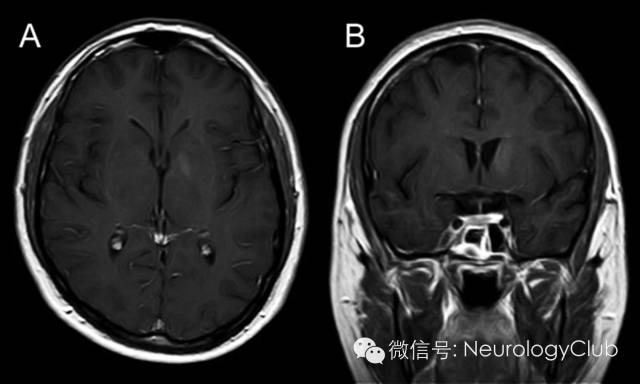

30岁男性,表现为面-臂肌张力障碍发作(faciobrachial dystonic seizures,FBDS)。发作期和发作间期的脑电图正常。脑脊液化验无殊。头颅MRI示左侧尾状核和苍白球强化病灶(图1)。血清LGI-1(富亮氨酸胶质瘤失活1蛋白)抗体阳性。全身CT扫描未发现恶性肿瘤。患者行5个周期的血浆置换后再接受长期的激素治疗,完全恢复。5月后复查头颅MRI,发现病灶强化信号减弱(图2)。LGI-1是一种与电压门控钾离子通道相关的分泌蛋白,在新皮质与海马区高度表达。LGI-1突变见于合并听觉症状的常染色体显性遗传颞叶癫痫(autosomal dominant partial epilepsy with auditory features,ADPEAF)。本例患者无ADPEAF的临床症状。关于FBDS是一种癫痫发作还是肌张力障碍仍存在争论。本例患者基底节区受累可与这一争议相关。

图1:治疗前增强MRI